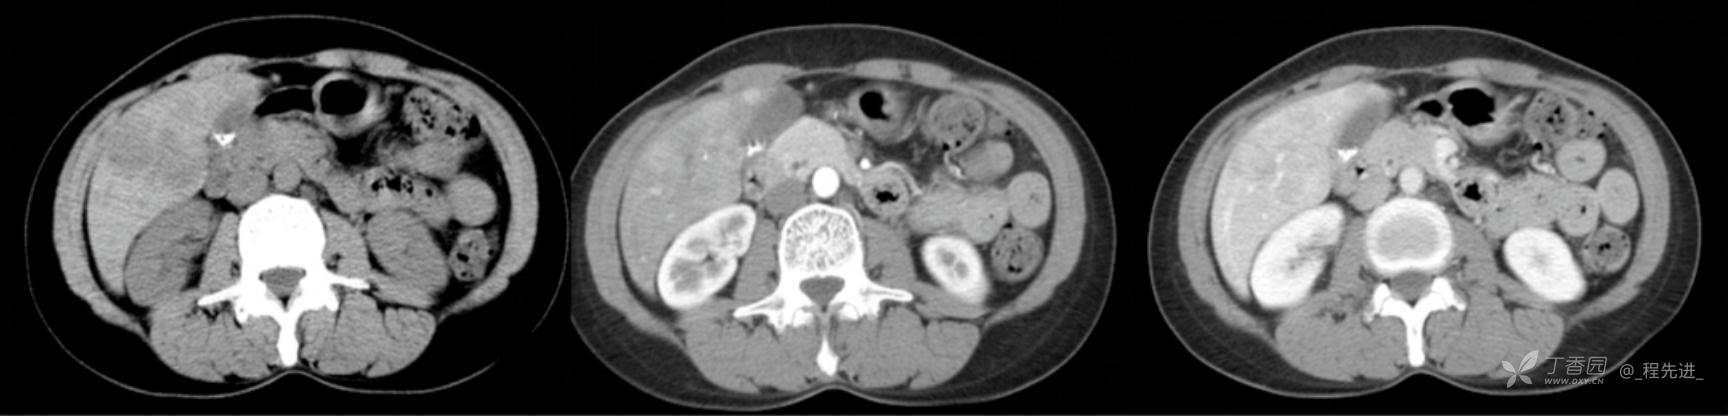

图像左边为平扫,中间的是动脉期,右边的是静脉期